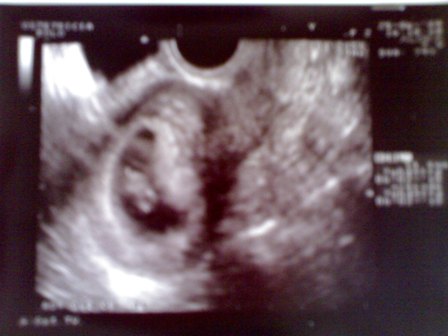

Amúgy jól vagyunk, Lilla is. Szépen fejlődik ő is kis Zsebi is. Most már Zsebi is mocorog rendesen a pocakban egy egy erősebb megmozdulást már apa is érez.